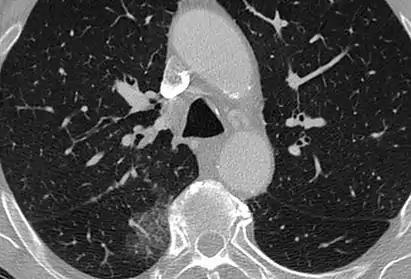

CT image showing ground-glass opacification in the posterior of the right lung (screen left). - Measles